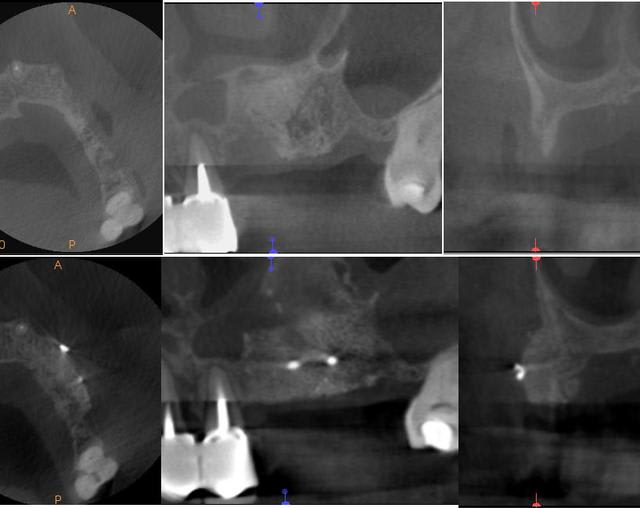

un petit cas pour montrer l'intégration des greffons allogène (biobank)

tekka 9 et 11 mm